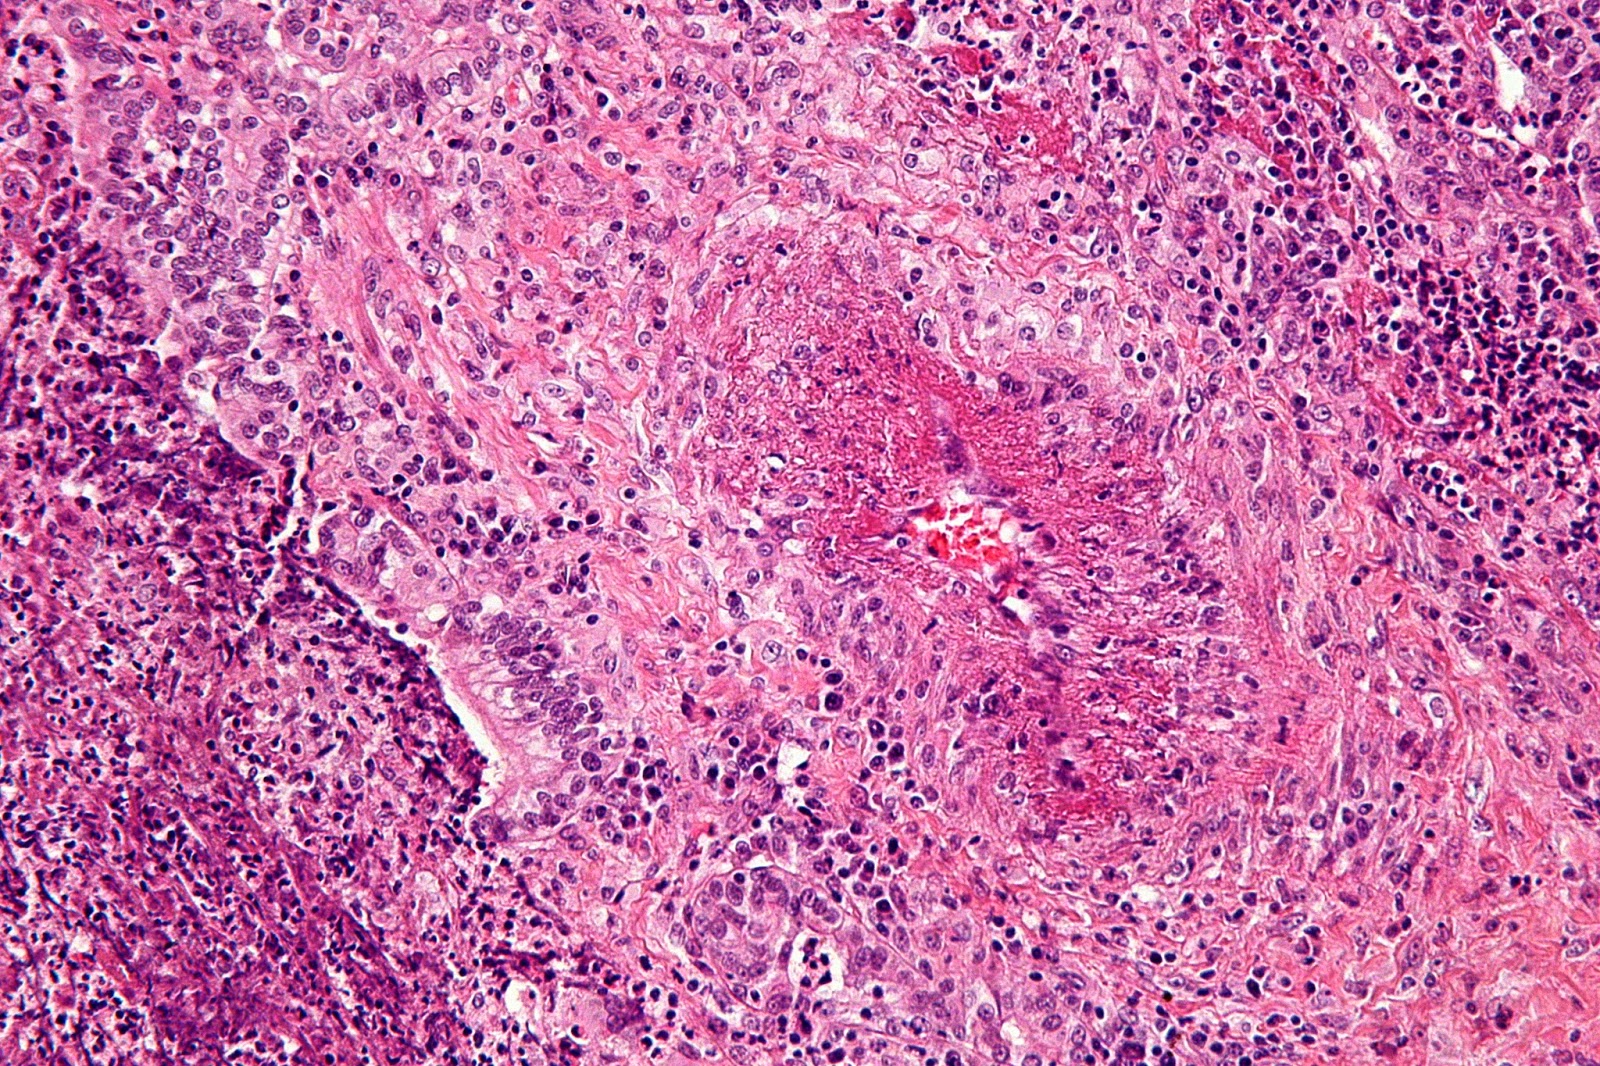

Clinical and Histological Features in Wegener Granulomatosis Wegener's Disease Wiki Granulomatosis with polyangiitis (gpa), previously known as wegener granulomatosis, is an autoimmune disorder. Granulomatosis with polyangiitis (formerly called wegener’s) is a rare disease of uncertain cause that can affect people of all. Granulomatosis with polyangiitis (gpa) is a potentially lethal systemic disorder that is characterized by necrotizing vasculitis of small. Granulomatosis with polyangiitis (gpa) is a rare condition where blood. Wegener's Disease Wiki.